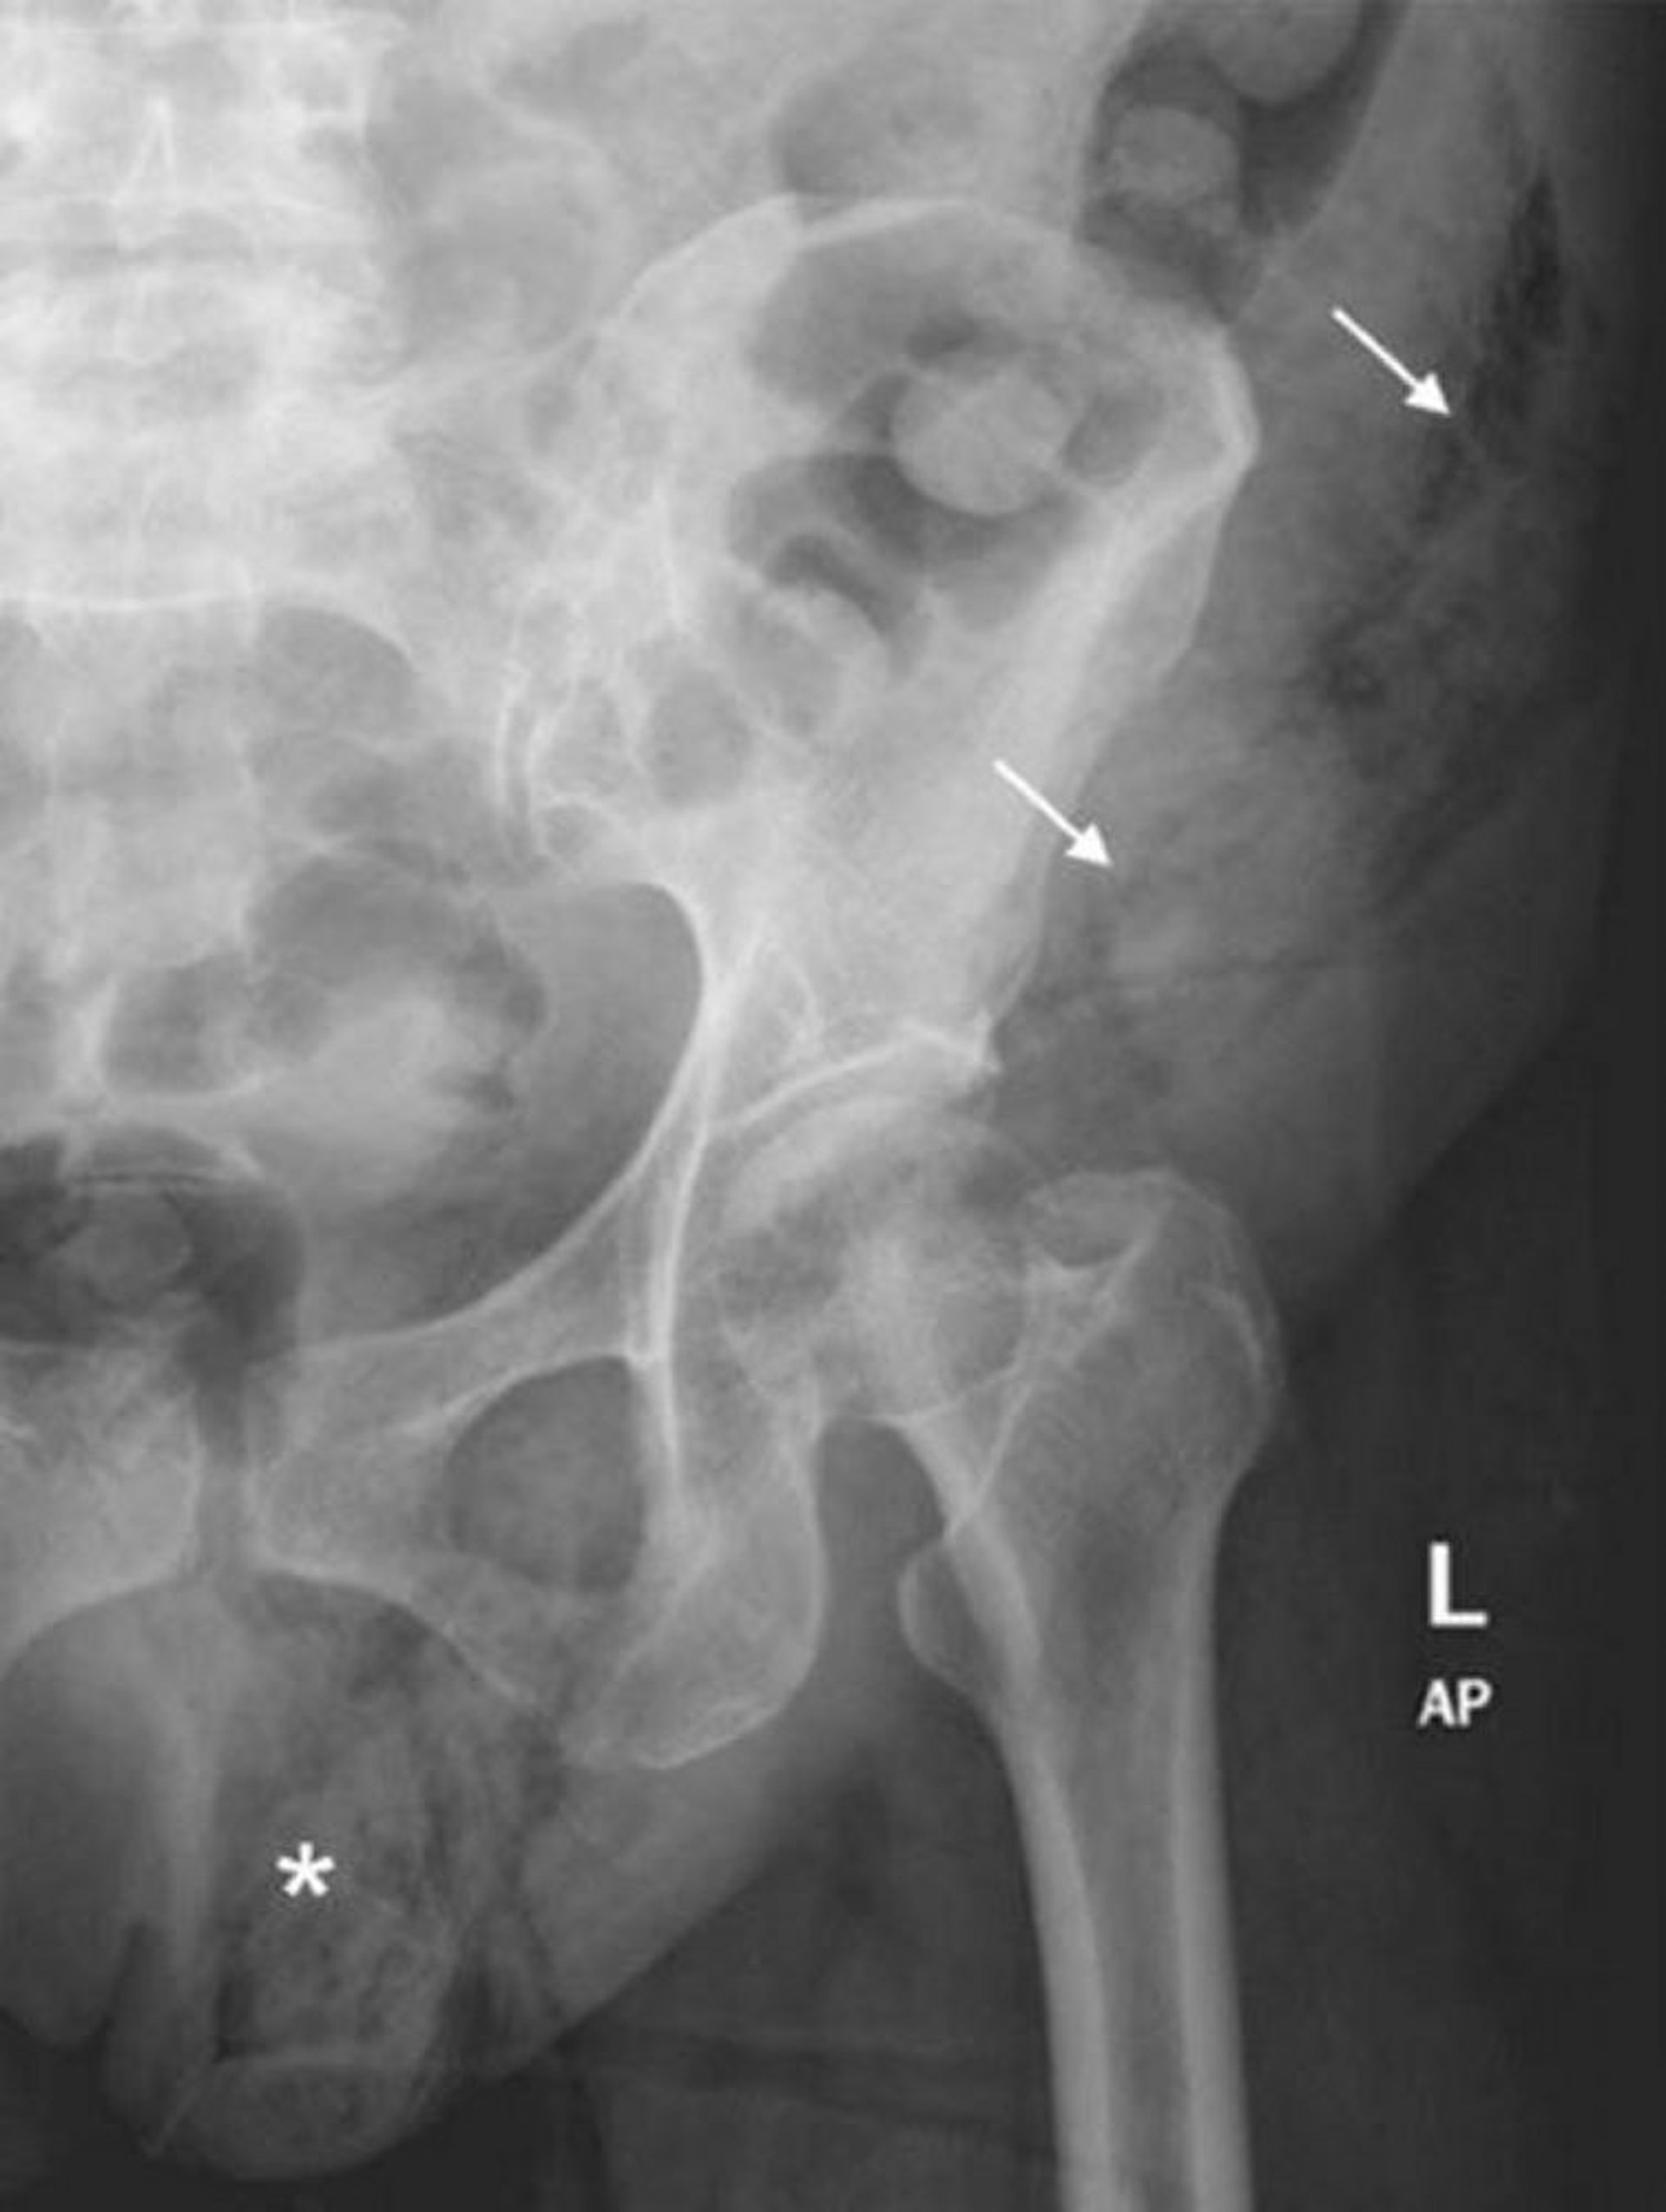

Gangrena de Fournier (Radiografia abdominal)

Essa radiografia de abdome mostra extensão dos gases dos tecidos moles do hemiscroto esquerdo (*) à parede abdominal esquerda (flechas).